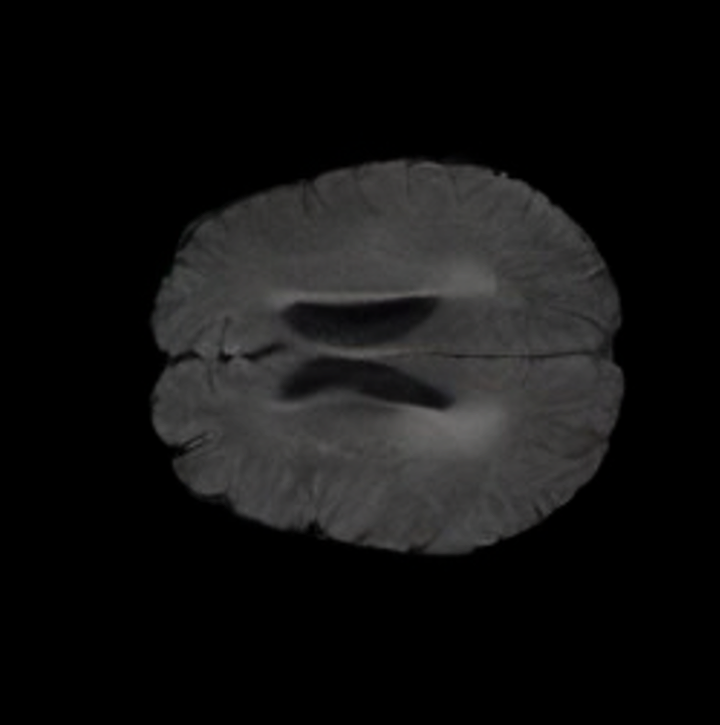

Notably, X-Diffusion achieves state-of-the-art dB for a few input slices while baselines require more than 60 input slices to achieve similar performance (Figure 7). The margin is more than 12 dB PSNR for the 1-slice input in both the BRATS and the UK Biobank benchmarks (see Table 1 and Figure 6). For reference, two randomly sampled MRIs from UK Biobank would have a PSNR of 15.95 dB 0.36 (on 4800 randomly sampled examples). Omitting the preprocessing step of alignment DXA to MRI, leads to a drop of PSNR on average by 2.87 dB (29.01 dB 26.14 dB). The slices from 3D reconstructed volumes at varying depths and axis of rotation, visually match the ground truths for both brain and whole-body scans (see Figures 4 and 5 left). We also plot the error map (Figure 3) and the spread of the error (Figure 5 right) of such X-Diffusion generations to highlight the differences with the ground truth MRIs.

The comparison of generated MRIs versus reference MRIs suggest a nearly perfect preservation of brain volume (in mm3) with median volume of reference MRIs of versus generated MRIs (see an example of brain generation in Figure II).